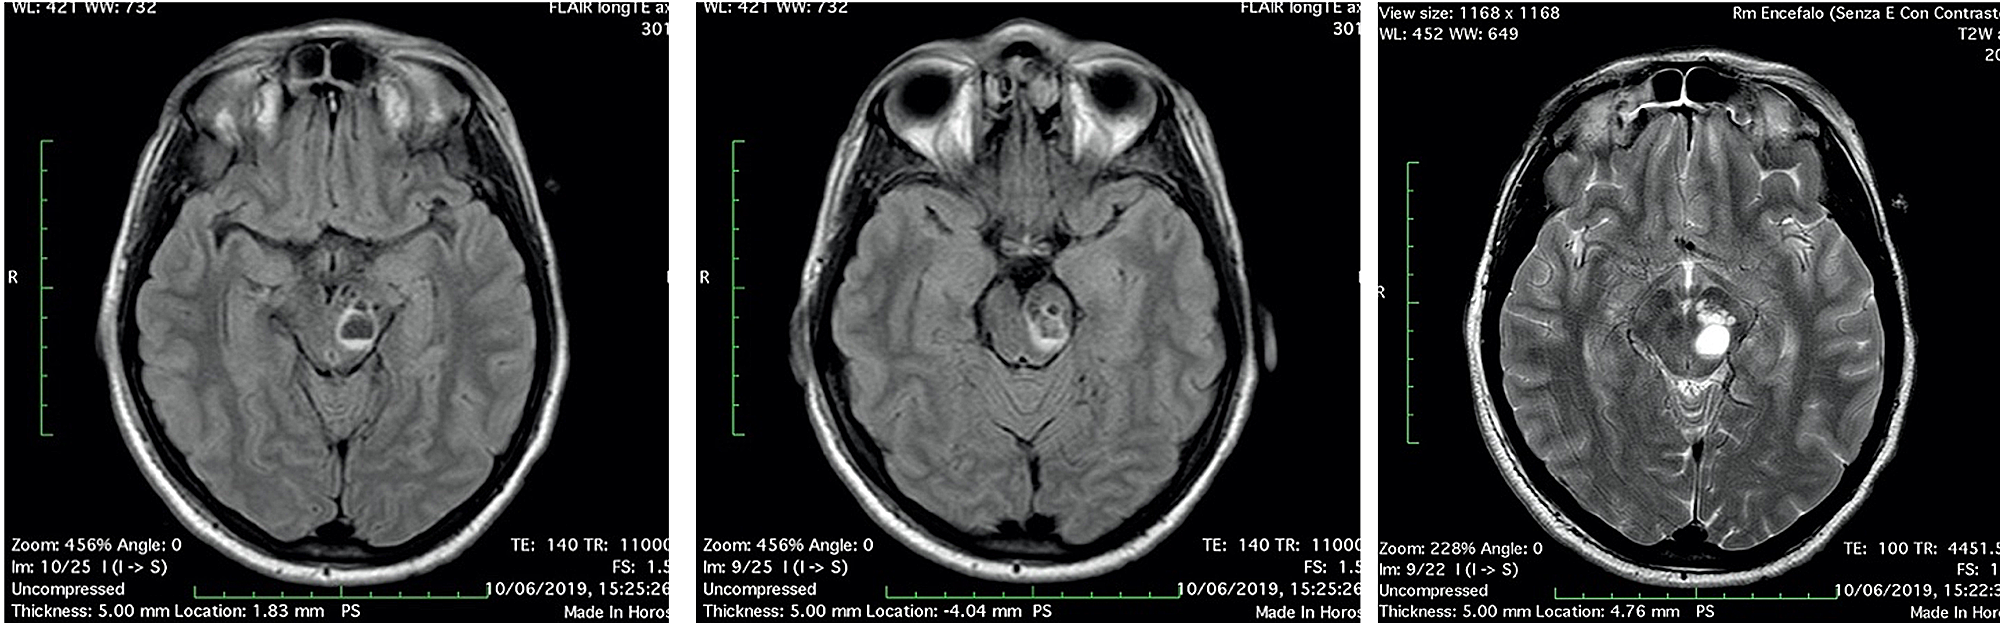

A 42-year-old woman, without previous disease, was admitted in the Emergency Room for a polytrauma during an accident car. Clinically she was conscious; she had a head trauma with hairy scalp; she complained headache and pain of the left foot; on the accident set, opiates were administered. Pressure of oxygen (PaO2) was 98%, cardiac frequency was 65 bpm, Glasgow Coma Scale was 15, and the neurological examination was negative. Laboratory tests revealed hemoglobin: 10.7 g/dL (normal range 12-16 g/dL), white blood cell: 11.71 x 109/L (normal range 4-10 x 109/L), coagulation tests in normal range, and normal platelet count. A total body CT was performed; it demonstrated, beyond the hairy scalp with large soft tissue loss in frontoparietal zone, a multiloculated cyst in the left midbrain, with eccentric hyper-density, hematic-like (Figure 1). An X-ray of the left foot showed a fracture of the first toe. In absence of neurological deficit, the patient immediately underwent surgery for the reconstruction of the scalp.

The first day after surgery, the patient was transfunded for hemoglobin 6.8 g/dL (normal range 12-16 g/dL), referring to scalp surgery. She complained headache, vertigo, nausea and diplopia, reflecting an involvement of the brainstem and the oculomotor nerves. A second CT and brain MRI with IV contrast were performed: CT scan showed a fluid-fluid level, with enlargement of left cerebral peduncle and a slight mass effect (Figure 2). MRI scan confirmed the same findings of fluid-fluid level, with enlargement of left cerebral peduncle and a slight mass effect; no contrast enhancement was observed: these findings were referred to enlargement of VRSs with post-traumatic bleeding. Neither SAH nor intracerebral hematomas were revealed (Figure 3). No neurosurgery was indicated but only clinical and imaging follow up.